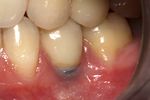

حالة الفم الصحية السيئة، والأمراض العامة الحادة والمزمنة، والتهاب النسج الداعمة paradontisis، والتهاب النسج الداعمة الحفافية، وفي حالة الضياع المادي الرضي لأكثر من ثلث الصفيحة السنخية الدهليزية.

إن أمام عملية غرس البدائل للأسنان طريقاً وعرة، إذ إنه مع تطور المواد المغروسة وحسن تقبلها من الأنسجة العظمية المحيطة، تبقى مشكلة بروز المهماز من الغرسة من خلال الغشاء المخاطي إلى جوف الفم قائمة، مما يجعل للغرسة وضعاً خاصاً تكون فيه على صلة بجوف الفم وبما يحمله من مجموعات جرثومية مؤذية لا يمكن منعها من اجتياز المنطقة المحيطة بعنق الغرسة إلى العظم. وتدل الإحصاءات العالمية الحديثة لنتائج الغرسات المطوَّرة من مادة التيتان، على وصول نسبة النجاح إلى 85% في خمس سنوات فما فوق من تطبيق الغرسة.